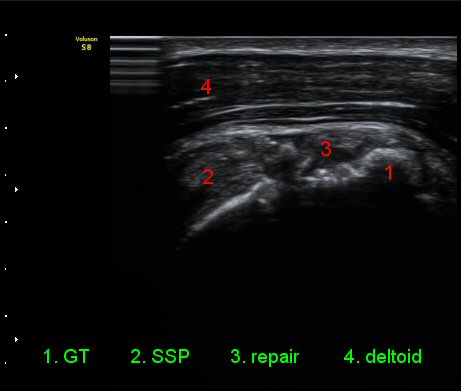

ÃÊÀ½ÆÄ °Ë»ç

ÀÌµÎ¹Ú±Ù°Ç È¾´Ü¸é°Ë»ç¿¡¼­ °ÇÁÖÀ§¿¡ ¼Ò·®ÀÇ ¼ö¾×Àú·ù¿Í Á¡¾×³¶³» ¾×Àú·ù°¡ °üÂûµÈ´Ù(»çÁø 1, 2).

¾î±ú¸¦ ³»Àü, ³»È¸Àü, ½ÅÀüÇÏ¿© ±Ø»ó°Ç°Ë»ç¿¡¼­ ±Ø»ó°Ç ÆÄ¿­ ÈÄ ¼ö¼úÇÑ ¼Ò°ß, ±Ø»ó°ÇÀÇ

Àú¿¡ÄÚ ºÎÁ¾°ú ºÎºÐÀû ÆÄ¿­, °í¿¡ÄÚ ºÀÇÕ»ç, ´ë°áÀýÀÇ ºÒ±ÔÄ¢º¯È­,À» º¸¿©ÁØ´Ù(»çÁø 6, 7, 8, 9)